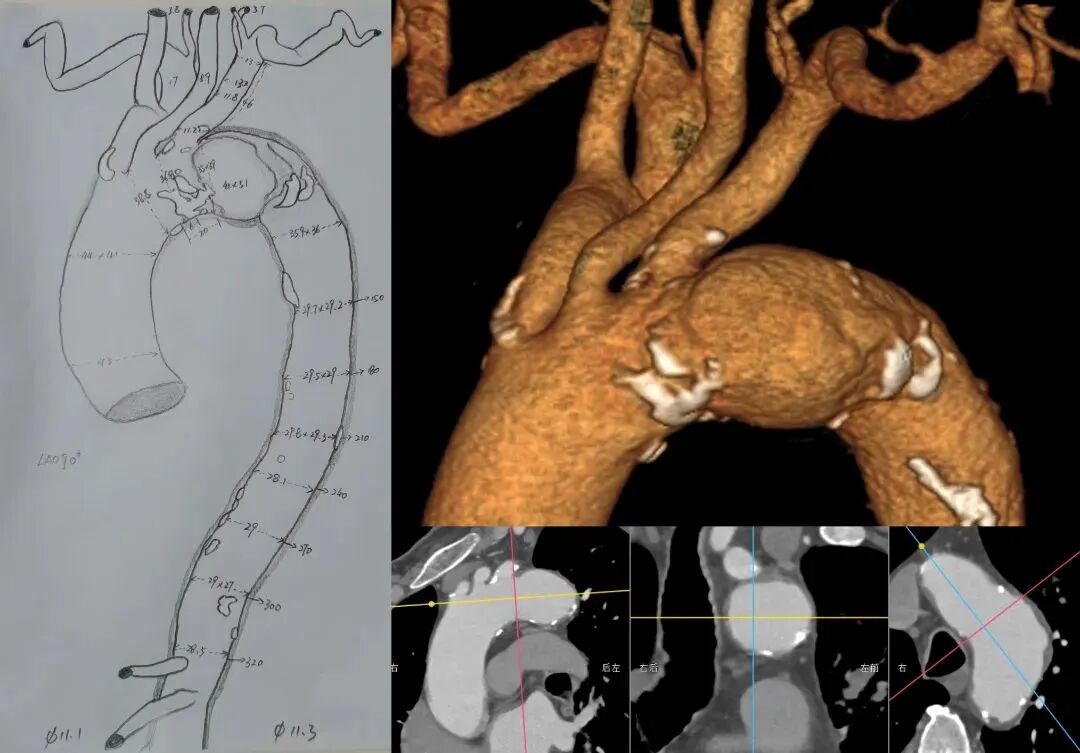

CTA详解:主动脉弓局部瘤样扩张,内径约51*42mm,近端已累及左锁骨下动脉根部。左锁骨下动脉迂曲,根部位于主动脉弓前壁,与主动脉成锐角仅30°。左颈总动脉距离左锁骨下动脉仅6mm。主动脉弓部及胸降主动脉管壁多发钙化斑块、非钙化斑块、混合斑块形成,局部管腔轻度狭窄;中央型肺癌并阻塞性肺炎;双侧冠状动脉走形区钙化斑。

术前三维重建

术前CTA横断面

测量数据